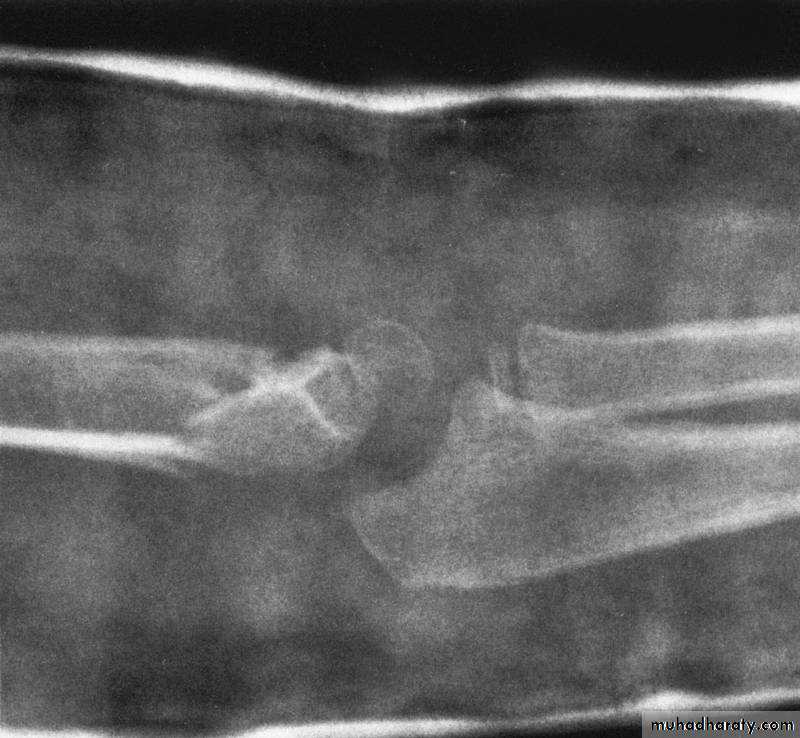

What type of supracondylar fracture

does this patient have?Flex

ionHow do the flexion patterns present?

This classical Type III pattern

is obviously a flexion injury.With these one needs to be

prepared to do an open reduction !!

8 y.o.

Is this a simple extension

type supracondylar fracture ??

It also has

anterolatateraldisplacement !!

The distal fragment is

not flexed,but also it is not extended to any degree.

This also is a Type III Flexion Pattern.